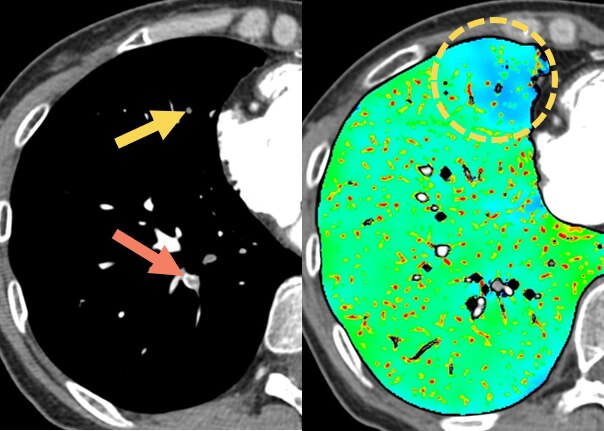

過去の検査時はどうしても至適心位相を探すため、segment再構成等を繰り返し撮影と画像検索を両立するのは困難でした。しかし、最適心位相検索に「Smart Phase」、モーションアーチファクトを抑制する 「SnapShot Freeze2.0(以下SSF2)」を併用することにより、最適心位相の検索をほぼ自動で行えるようになりました。結果、心臓CTの最適心位相検索に時間を割く必要がなくなり、人員配置の最適化を行えるようになると考えています。